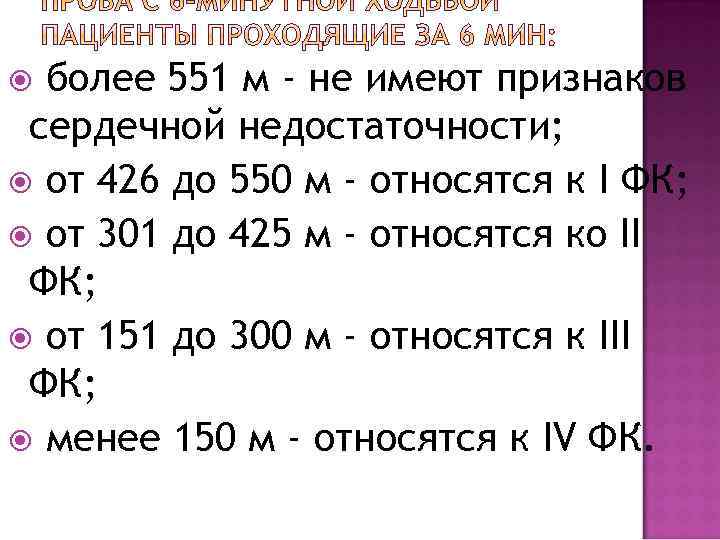

более 551 м - не имеют признаков сердечной недостаточности; от 426 до 550 м - относятся к I ФК; от 301 до 425 м - относятся ко II ФК; от 151 до 300 м - относятся к III ФК; менее 150 м - относятся к IV ФК.

более 551 м - не имеют признаков сердечной недостаточности; от 426 до 550 м - относятся к I ФК; от 301 до 425 м - относятся ко II ФК; от 151 до 300 м - относятся к III ФК; менее 150 м - относятся к IV ФК.